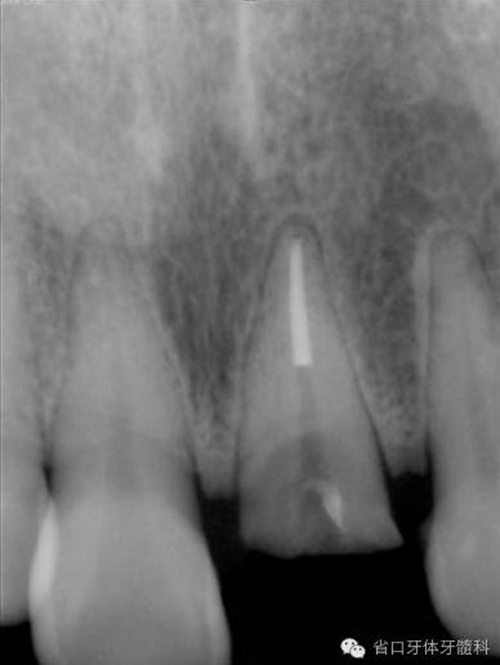

圖8. 21/行根管治療術(shù),保留根尖約5mm的根充物,根中上段預(yù)留空間以預(yù)備纖維樁道。

圖9. 腭側(cè)電刀切齦止血、暴露斷面,殘根斷面磷酸酸蝕